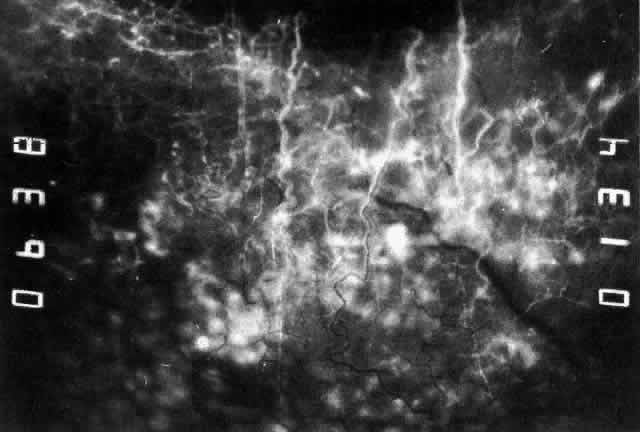

The characteristic features of necrotizing scleritis on fluorescein angiography are hypoperfusion and, eventually, nonperfusion of the vascular networks (Figs. 40 through 43).26 The initial changes are on the venous side of the capillary network; the transit time of the dye increases even if the eye is red and congested. If the disease process persists or has been present for a long time, thrombosis and permanent vaso-occlusive changes occur. These vessels (or the occluded capillary network) are bypassed by the opening of anastomotic channels. New vessels in a granuloma give rise to deep intrascleral leakage of dye (see Fig. 43). Conjunctival and episcleral involvement by the destructive change is late but is always preceded by vaso-occlusive changes that can sometimes be detected with use of the red-free light on the slit lamp (Figs. 44 and 45).

Fig. 40. Early necrotizing scleritis. There is characteristic yellow discoloration of the sclera underlying the conjunctiva at a point of necrosis. In this instance a small filament of tissue has penetrated the conjunctiva.

Fig. 41. Late stage of fluorescein angiogram adjacent to the site of necrosis in the same patient as in Figure 40. Although the eye is uniformly congested, the area near the necrosis shows vascular shutdown, whereas the rest of the conjunctiva and episclera is normally perfused.

Fig. 42. Late arterial phase of fluorescein angiogram in a patient with necrotizing scleritis. All the vessels except the main trunk and the vessels around the limbal perforating vessels are occluded and remain unperfused throughout the angiogram.

Fig. 43. Late venous phase of angiogram of a patient with necrotizing scleritis showing late deep leakage from vessels on the surface of the sclera and leakage of the capillary network at the limbus and the vessels draining it, together with poor or absent perfusion of the remaining vessels.